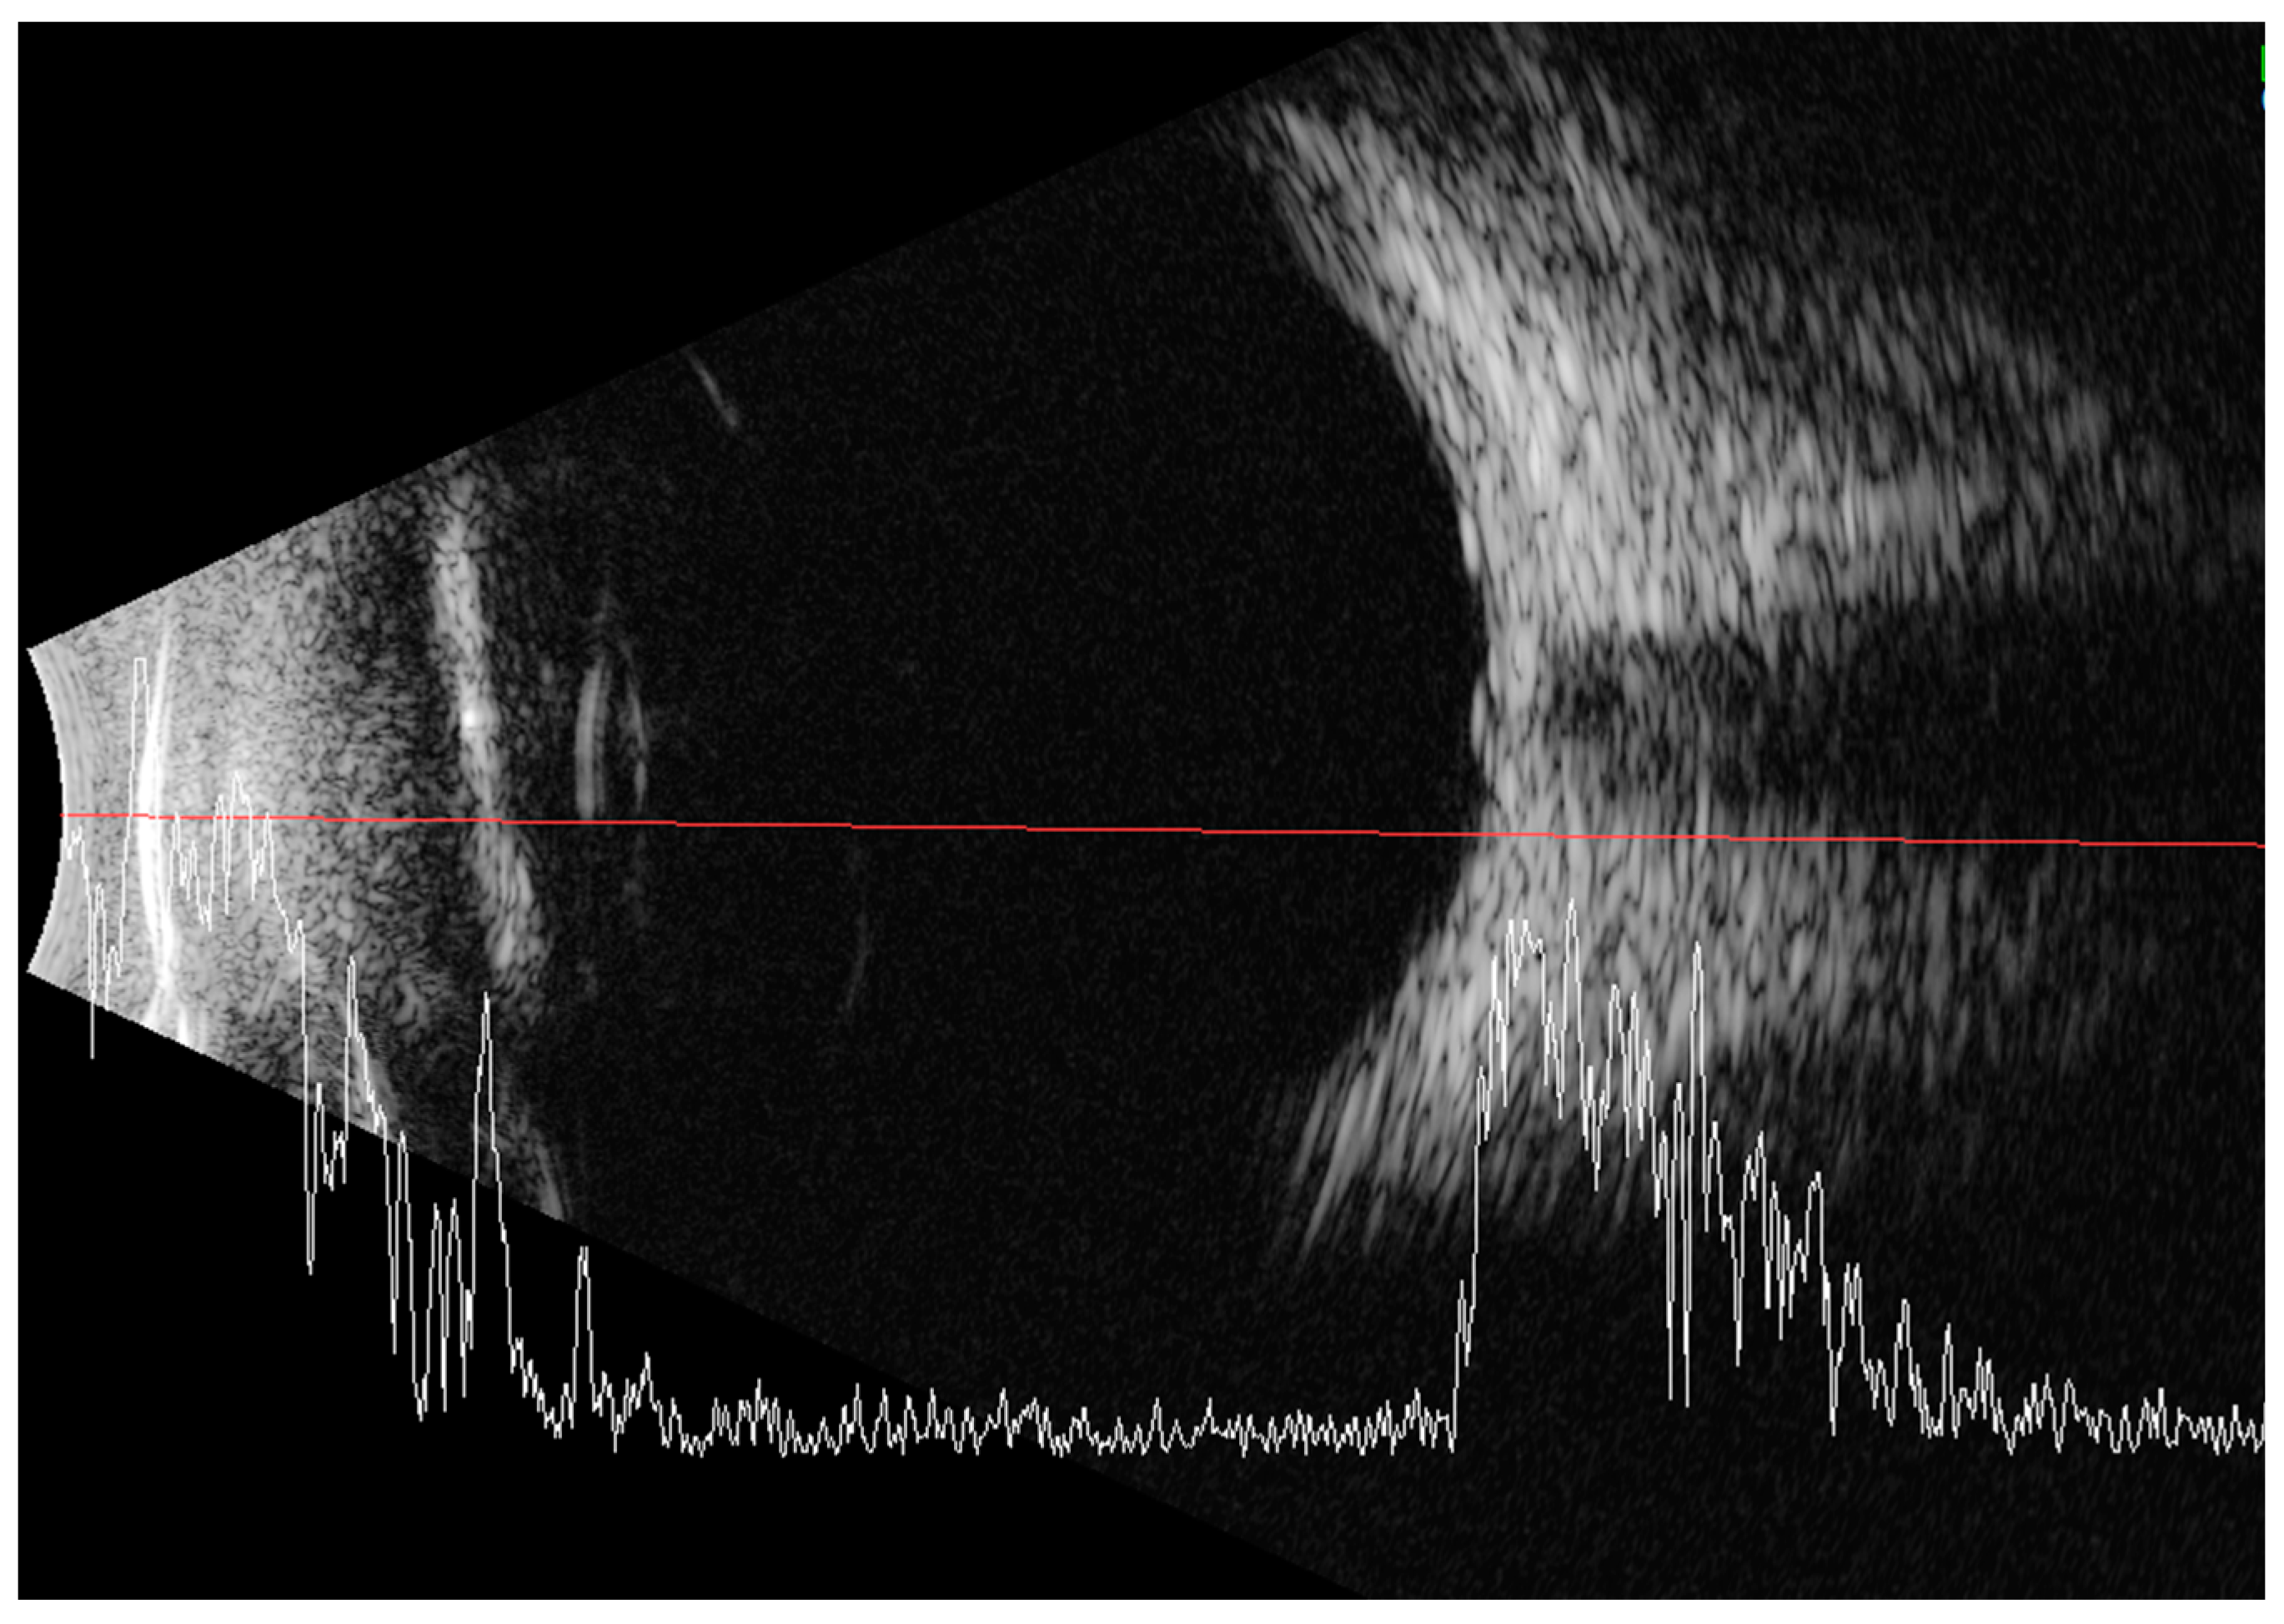

Less than a year later, the patient had a second visit in our outpatient clinic. According to her mother’s statement, for some time the girl showed worse interest in her surroundings. The patient’s RE did not follow objects (neurologic and developmental causes related to the underlying disease cannot be ruled out), while LE was following objects. The pupil response to indirect and direct light, as well as the swinging light test were normal. Anterior segment eye examination revealed a total cortical cataract in the RE and a partial cortical cataract in the LE. Evaluation of the RE fundus was impossible due to total cataract, fundus of the LE was poorly visible with noticeable optic nerve rim pallor. The USG examination of the RE showed increased echogenicity in the projection of the optic nerve disc and increased echo of the lens, while in the LE it was normal (Figure 3). An FVEP was performed to assess the patient’s visual potential, but due to very difficult cooperation, it was only possible to obtain a record from the RE (Figure 4).

Figure 3.

Ultrasound of the RE: increased echogenicity of the lens (cataract) and a slight punctate increase in echogenicity in the projection of the optic disc (which may correspond to external drusen).